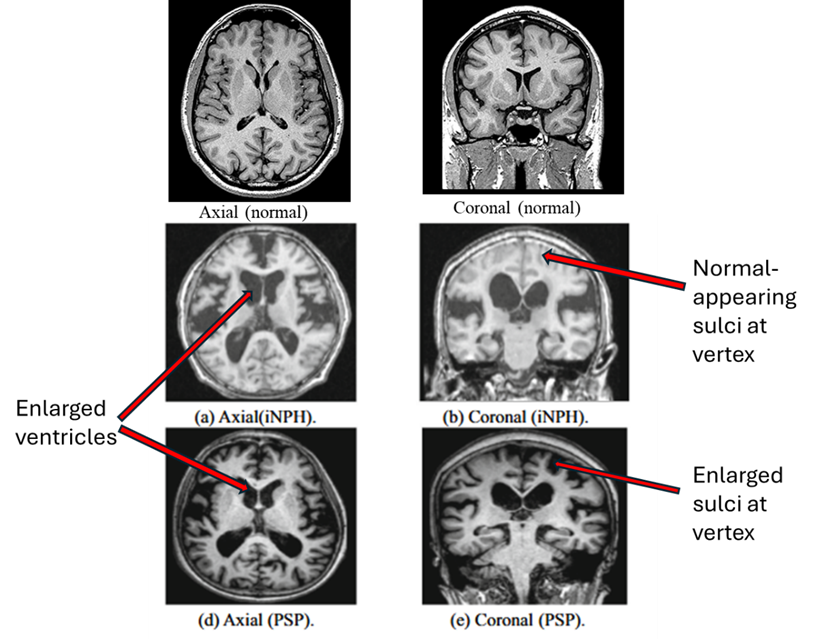

A. MRI diagnosis. Below are MRI images from idiopathic NPH (middle row) and PSP (bottom row). The main differences between PSP and NPH are indicated by the labels on the right. PSP features widening of the spaces between the brain’s folds caused by atrophy of the brain tissue. But in NPH, the spaces toward the top of the brain are as tight as, or tighter than, normal. There are other, less reliable, MRI differences, none of them adequately sensitive or specific for NPH.